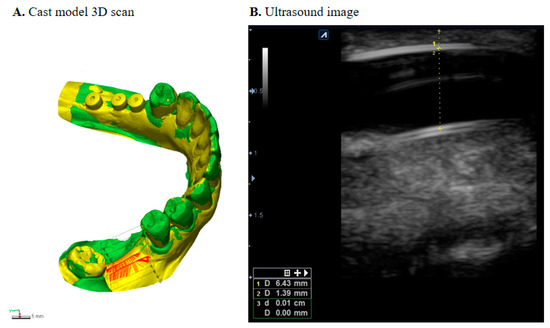

Outcome measures were collected at visit I (pre-operative), visit IV (tissue expander removal), and at visit VI (6 months after bone graft). Cast models were scanned with a 3D scanner (Trios3®, 3Shape, Denmark) and transferred into a database integrated software (Geomagic Control X, 3D systems, USA) to measure soft tissue dimensional changes (Figure 3A). Scanned 3D images were exported as STL files (standard tessellation language), and each patient’s images at different time points were superimposed using adjacent teeth from the defective site as the reference point and landmark as the best-fit initial alignment [21,22]. Three vertical cross sections and three horizontal cross sections were measured to observe the horizontal and vertical changes. For the vertical change, a cross-section was drawn as a plane crossing the central fossa, then two parallel planes 3 mm right and left of the central plane were drawn at the buccal and lingual sides, respectively. Horizontal dimensional change was measured with points 2, 4, and 6 mm from the cemento-enamel junction of adjacent teeth. The RMS (root mean square) estimate values were recorded for each pair, and their mean changes were calculated.

2.3.3. Thickness of Expanded Gingiva

Ultrasound images were obtained using E-CUBE 9 Diamond imaging system (Alpinion medical systems®, Seoul, Korea) at visit IV. An intraoral transducer IO3-12 (3~12 MHz frequency) was used to collect the thickness of the attached gingiva as well as possible thinning of the mucosa (Figure 3B).

3. Results

A total of 75 patients were screened for the study, and 66 patients were considered suitable from which 9 dropped out. A total of 57 patients were included in the final analysis. Further details on descriptive statistics can be found in Table 1. TET and TEG groups received an insertion of self-inflating osmotic expanders (mean 31.4 days) before bone augmentation. Mean soft tissue measurements at the end of its expansion (visit IV) were similar in both TET and TEG groups with its average vertical and horizontal expansion being 5.62 and 6.03 mm, respectively. Ultrasonographic measurements of gingival thickness overlying the expanders revealed that mucosa was not thinned post tissue expansion (pre-expansion thickness 1.24 ± 0.24 mm; post-expansion thickness 1.08 ± 0.34 mm, n = 27, p > 0.05), indicating minimal clinical risk of dehiscence during the expansion.

Figure 3. (A) Superimposition analysis for the measurement of soft tissue changes. (B) Ultrasonographic measurement of gingival thickness.